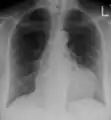

Ultrasounds showing a pericardial effusion in someone with pericarditis

A pericardial effusion as seen on CXR in someone with pericarditis